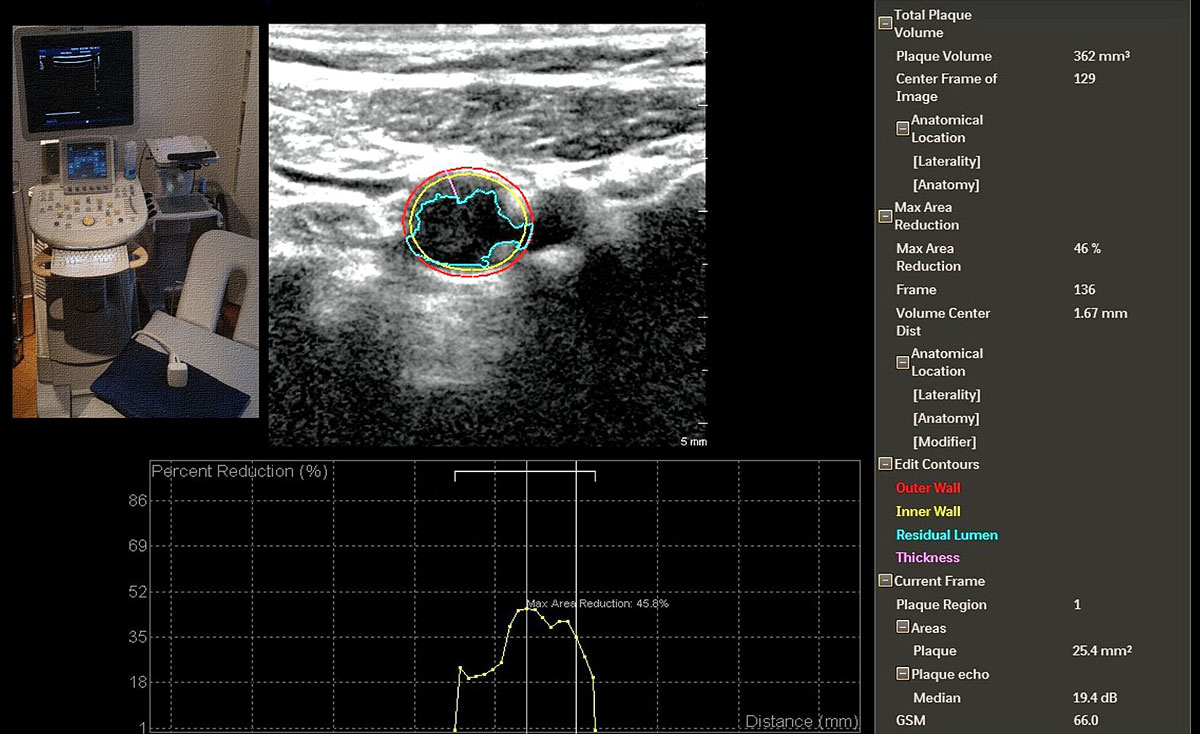

The sum of the longitudinal area of all plaques in the carotid wall is termed total plaque area (TPA) and is measured from the clavicles to the jaws using multiple angles to obtain the longitudinal circumference of all plaques in the carotid tree, with inclusion of the proximal brachial artery if possible [22] (fig. 4). Recently, carotid plaque volume has been made available by use of the Philips iU 22 ultrasound system equipped with a single sweep volumetric transducer (fig. 5), which covers 3.8 cm of the carotid artery and visualises the distal part of the common carotid artery, the bulb and the proximal parts of the internal carotid artery [23] (and personal communication Philips AG, Zurich, Switzerland). Off-line software calculates the plaque areas from all obtained transversal images in order to calculate the total plaque volume (TPV). Since the field of view is only 3.8 cm, some plaques proximal or distal to the transducer are missed and these plaques are included in the total plaque area derived from longitudinal carotid images (fig. 4). The advantage of the longitudinal plaque imaging (TPA technique) is its high reproducibility [24], vendor independence (no additional costs for surface tracings) and the possibility to obtain the results without additional software [14]. The definition of atherosclerotic plaque versus non-atherosclerotic intimal thickening has not been used uniformly in the literature (table 1). For clinical purposes, an IMT increase of >1.5 mm or a focal thickening of >50% when compared with adjacent structures is the most commonly used approach [15].

Figure 5 Semiautomatic measurements of transversal plaque areas obtained from a Philips iU 22 ultrasound system equipped with the single sweep volumetric transducer vL 13-5. Analysis was performed offline with software provided by the manufacturer. The software calculates the total plaque volume from all transversal carotid plaque areas obtained by the single sweep volumetric transducer over a field of view of 3.8 cm.